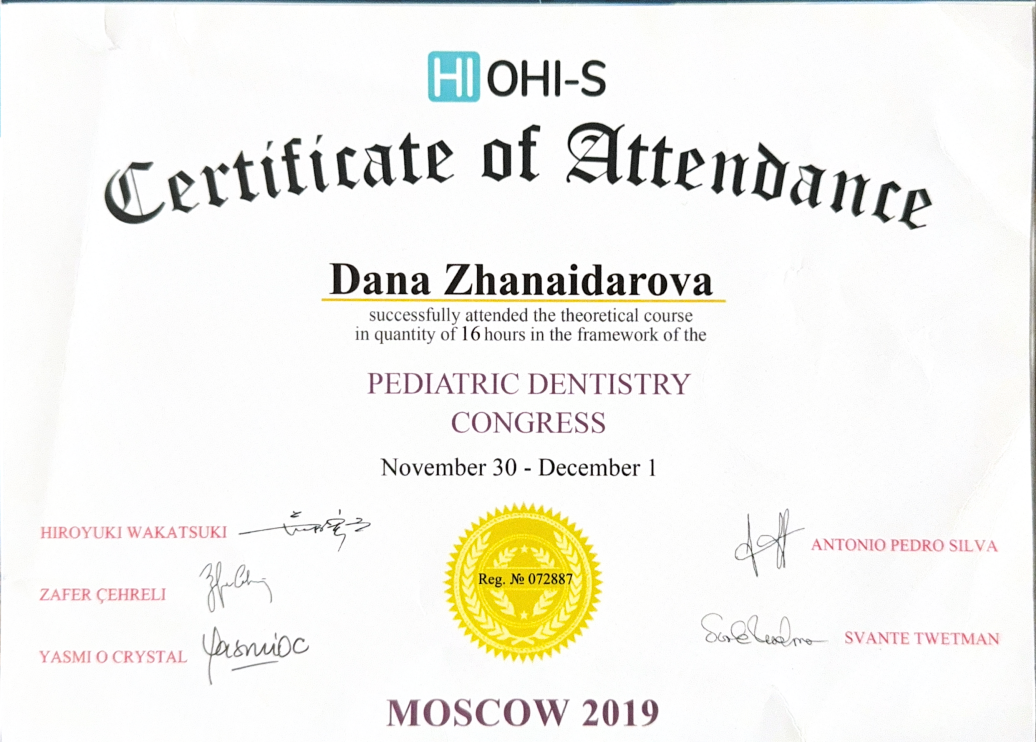

Регулярно совершенствует знания в стоматологии